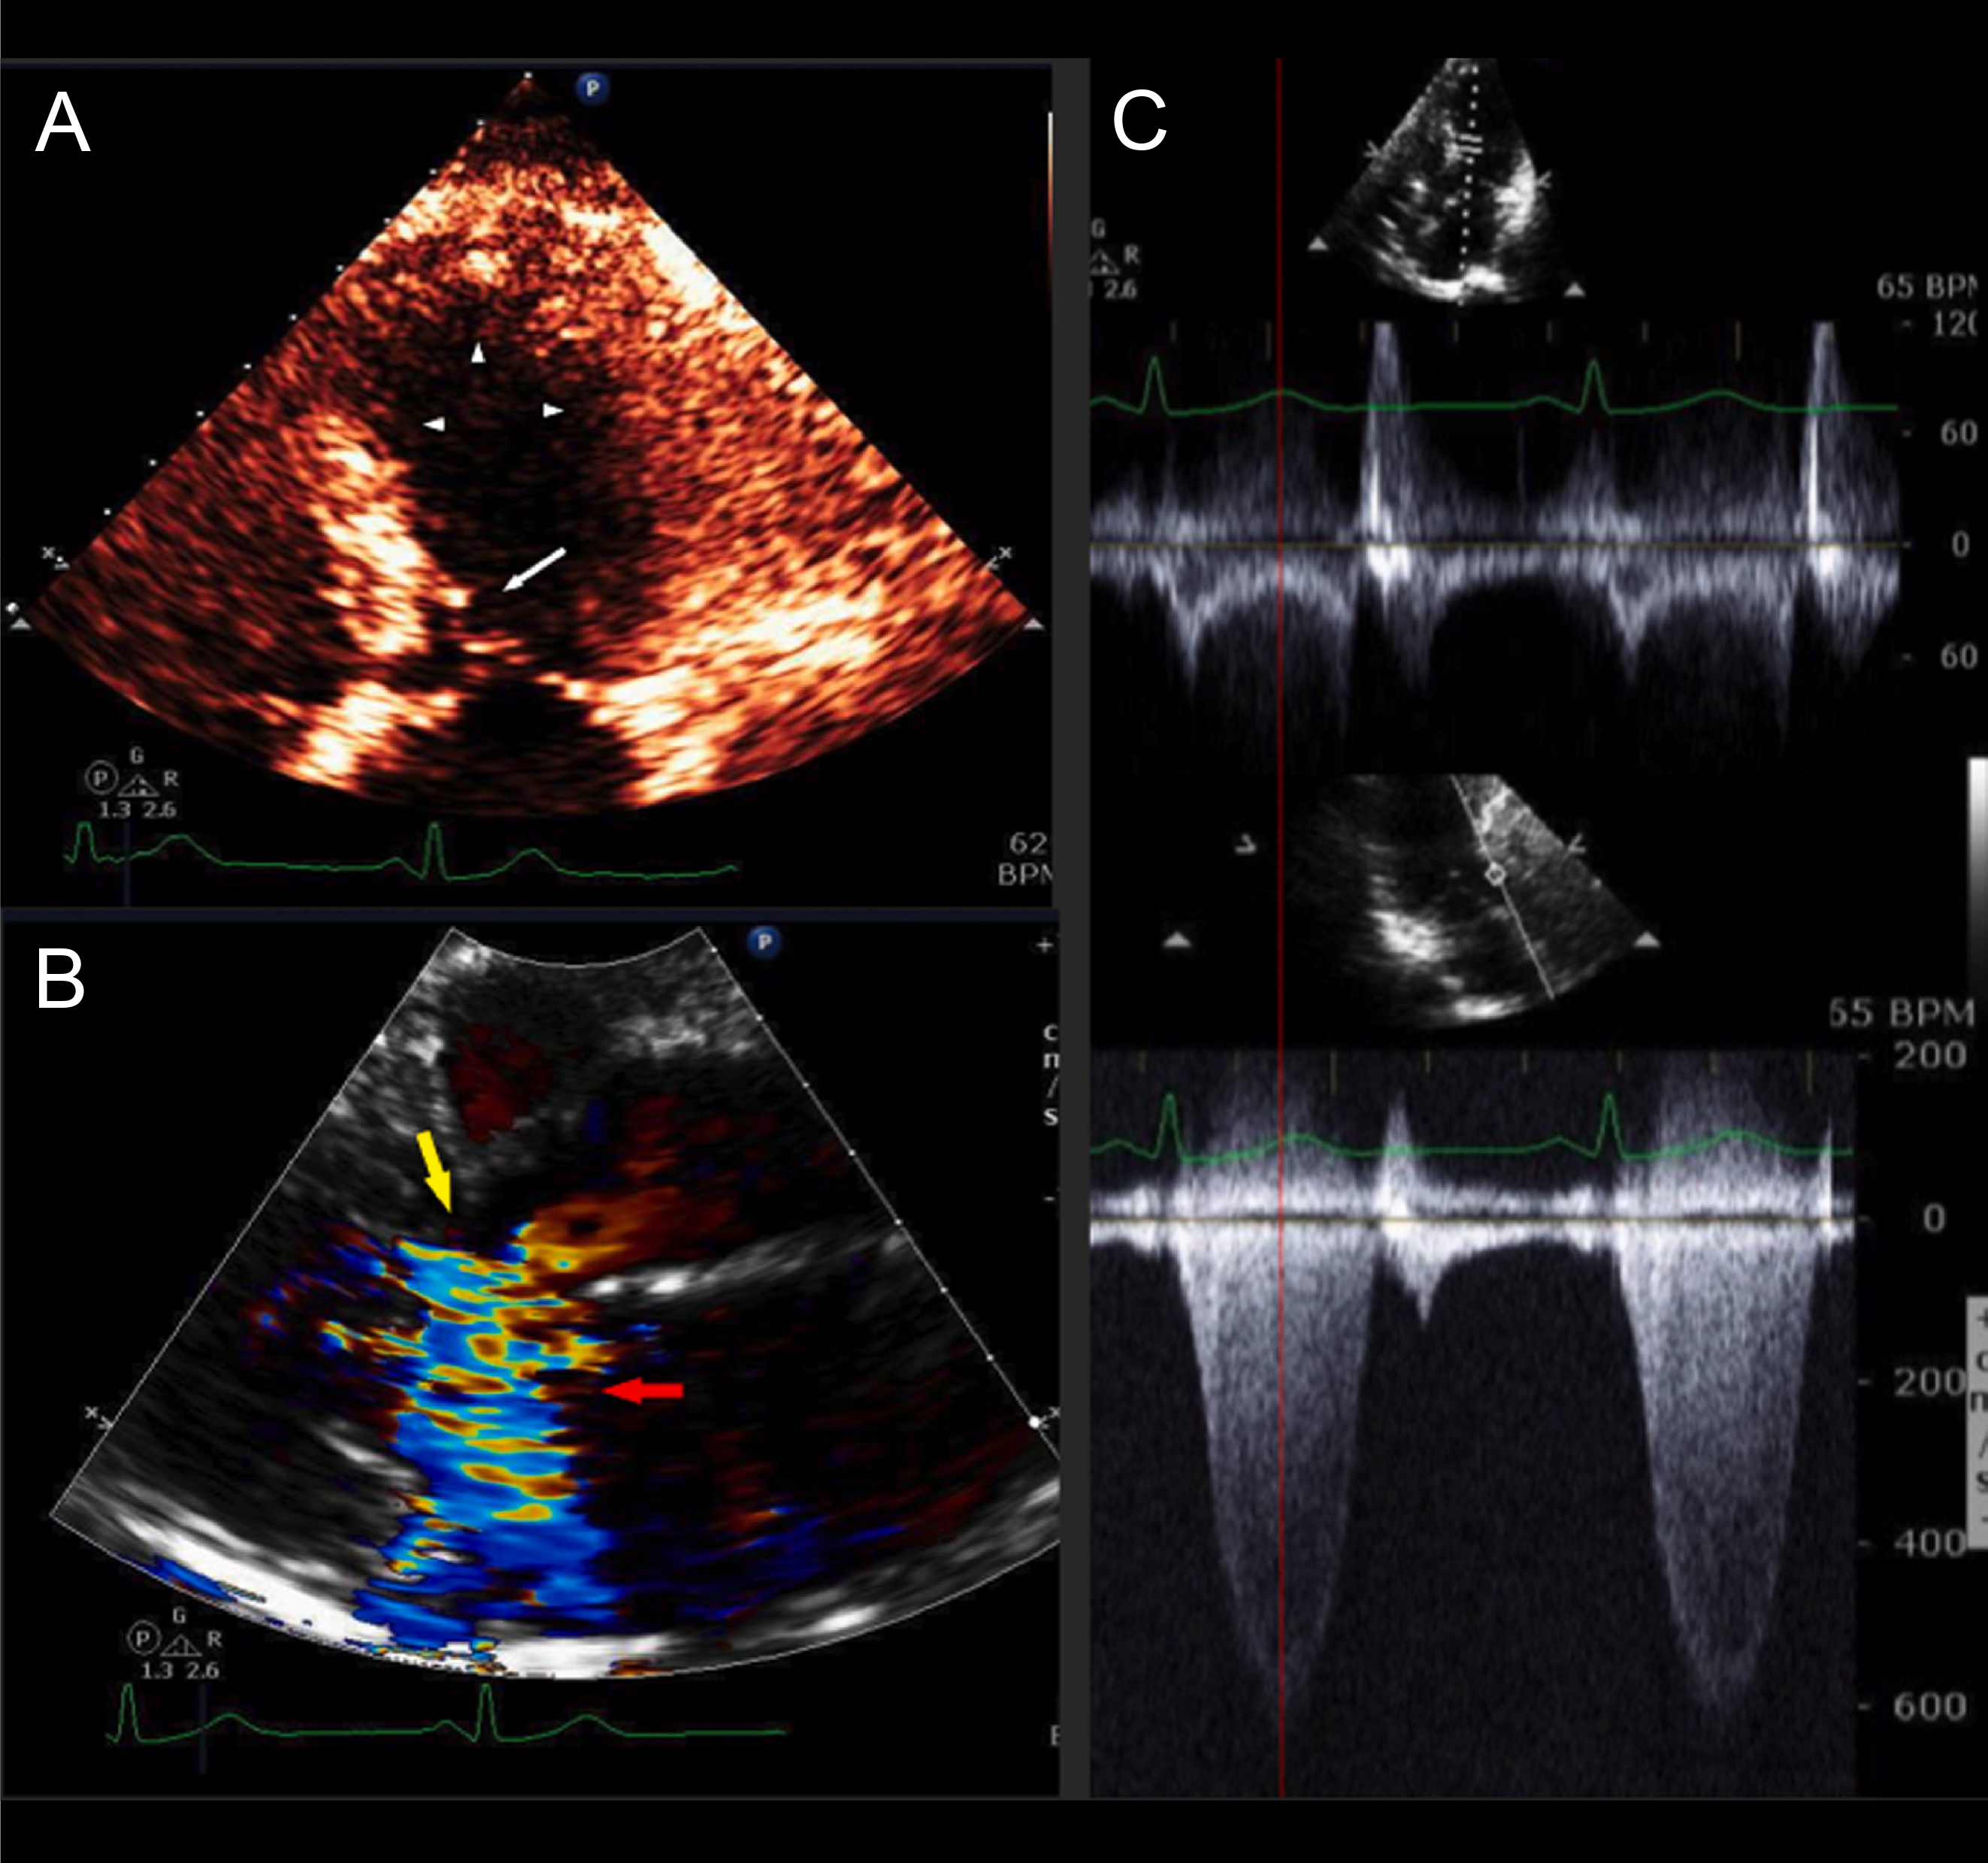

The clinical presentation of patients with obstructive HCM with LV ballooning share several overlapping features with TTS. Patients with these syndromes typically have chest pain, dyspnea, syncope, ST-segment changes on ECG, and elevated cardiac biomarkers, consistent with acute coronary syndrome (Fig. 3 (Ref. [9]) and Fig. 4) [7, 42]. The initial diagnostic workup for both conditions includes transthoracic echocardiogram (TTE), which typically shows apical hypokinesis with basal hyperkinesis. Coronary angiography excludes obstructive disease in both conditions [40].

Fig. 3.HCM with mild asymmetric septal hypertrophy, LVOT obstruction, and acute apical ballooning syndrome. A 63-year-old woman was admitted with near-syncope, hypotension, and NSTEMI (troponin I of 0.64 ng/mL). Coronary arteries were angiographically normal. LV cineangiography revealed acute apical ballooning. Left heart catheterization revealed an aortic pressure of 89/51 with a gradient of 100 mmHg. Following intravenous metoprolol, the patient’s outflow tract gradient improved to 40 mmHg, and her BP improved to 105/80 mmHg. A stress TTE performed 22 months after presentation demonstrated normal LV wall motion and no resting gradient. Following stress, TTE revealed mitral-septal contact and a peak LVOT gradient of 81 mmHg. This patient had very mild septal thickening HCM with acute apical ballooning due to LVOT obstruction presenting clinically as TTS. After recovery of LV systolic function, she continued to have severe LVOT gradients provocable after exercise. (A) Echocardiogram performed on admission (systolic frame) revealed apical and mid-LV ballooning with severe hypokinesis (arrowheads) and mitral-septal contact (white arrow). (B) Color Doppler (systolic frame) demonstrated severe mitral regurgitation (MR) (red arrow) and turbulence in the LV outflow tract (yellow arrow). (C) Pulsed-wave (PW; top) and continuous wave (CW; bottom) Doppler tracings obtained on admission TTE. PW Doppler at the level of the LVOT revealed a mid-systolic drop in PW Doppler velocities (“lobster claw abnormality”). The nadir in the drop of the PW Doppler corresponds to the peak of the CW gradient in the outflow tract (139 mmHg, bottom), as shown by the red dotted line. The PW velocity in mid-systole is low at 20 cm/sec, due to LV systolic dysfunction. Reproduced with permission Am J Cardiol [9]. HCM, hypertrophic cardiomyopathy; LVOT, left ventricular outflow tract; NSTEMI, Non-ST segment elevation myocardial infarction; LV, left ventricle; TTE, transthoracic echocardiogram; TTS takotsubo syndrome.